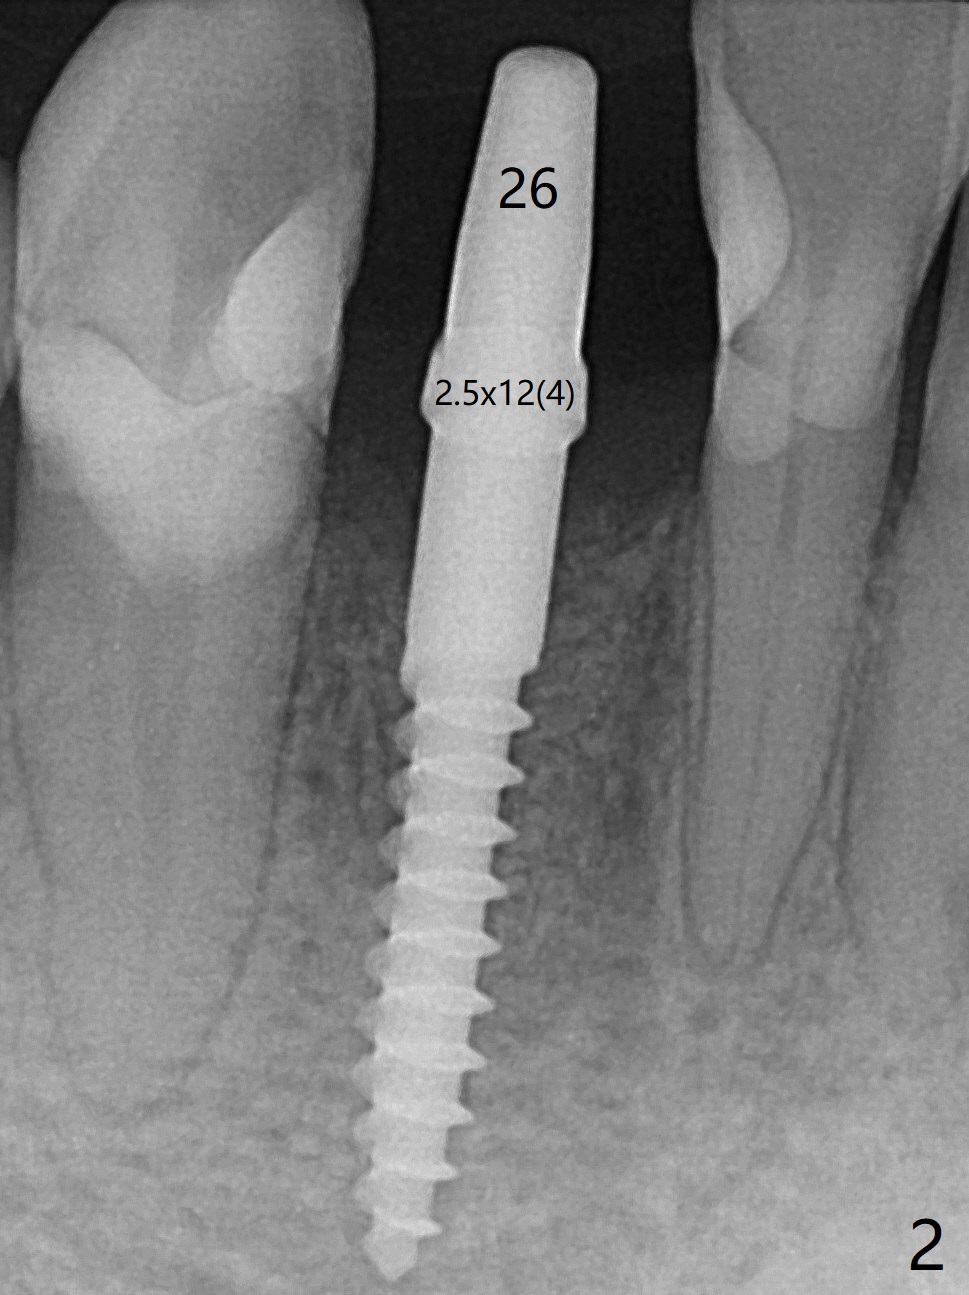

术前检查植牙位点角化龈,好像不太成熟(23,29号牙位点保存2个月,26号牙4个月),所以切开。翻瓣后,放置导板,29号牙位有意减少钻洞直径,用完3毫米钻头后,颊侧骨板已经薄,因此放入3.8x8.5毫米植体(设计4.5x8.5),颊侧植体顶端略微暴露,种深0.5毫米,之后颊侧放置自体骨和异体骨(图一:*)。26号牙钻洞也偏颊侧,所以选择4毫米袖的一段式植体,可以种深(图二,与图三对比),植入自体骨后,使用胎盘膜覆盖。由于没有特别一段式植体导板钻头,最细钻头2.2毫米,所以扭力低,没有即刻修复,下次应该减少钻洞深度,增加扭力。